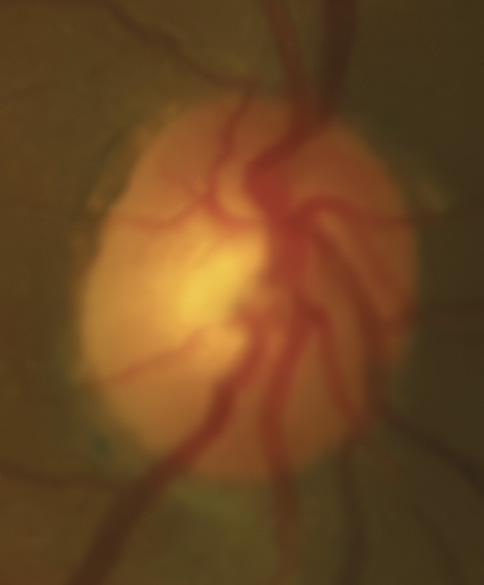

A 46-year-old African American male presents for glaucoma quarterly monitoring. Medical history is positive for hypertension controlled with 50 mg hydrochlorothiazide and reports no diagnosis of diabetes mellitus or known drug allergies. Ocular history is positive for progressive myopia bilaterally and pigment dispersion syndrome converting to pigmentary glaucoma right eye mild, left eye moderate with treatment initiated in September of 2016. The pigmentary glaucoma was treated with 0.005% latanoprost in both eyes every evening. There was positive family history of glaucoma (patient’s father). Best corrected visual acuity was measured at 20/25 in each eye. Pupillary assessment revealed a stable 1+ afferent pupillary defect in the left eye. Confrontation fields were full to finger count in the right eye and superonasal constriction in the left eye. Extraocular motilities were full with no restrictions or report of diplopia in both eyes. Slit lamp examination is remarkable for a Krukenberg spindle (Figure 4) bilaterally and a Zentmeyer line (Figure 5) in the left eye. Intraocular pressures at 3:30 pm via GAT measured 18 mmHg right eye, 23 mmHg left eye. Gonioscopy was performed and revealed open angles to ciliary body with a concave iris configuration and 4+ trabecular meshwork pigmentation (Figure 6) and the posterior corneal surface. There was no pigment attached to the anterior lens surface. The highest recorded intraocular pressures prior to treatment were 27 mmHg right eye & 35 mmHg left eye. CCT measured 554 microns in the right eye and 538 microns left eye. Optic nerve head assessment revealed bilateral intact neuroretinal rims with vertical elongation greater in the left eye than the right with inferior neuroretinal rim thinning in the left eye (Figure 7).

Bild 7: Fall 2 – (a) Sehnervenkopf OD, (b) Sehnervenkopf OS

CD ratios were estimated horizontally/vertically as 0.4/0.5 right eye, 0.6/0.8 left eye. Repeat testing of 24-2 Humphrey Visual Fields (HVF) (Figure 8) and optic nerve head optical coherence tomography (OCT) (Figure 9) were obtained.